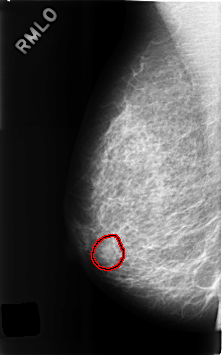

C_0311_1.RIGHT_MLO

RIGHT_MLO LINES 4608 PIXELS_PER_LINE 2888 BITS_PER_PIXEL 12 RESOLUTION 50 OVERLAY

FILE: C_0311_1.RIGHT_MLO.OVERLAY

TOTAL_ABNORMALITIES 1

ABNORMALITY 1

LESION_TYPE MASS SHAPE ROUND MARGINS OBSCURED

ASSESSMENT 3

SUBTLETY 2

PATHOLOGY BENIGN

TOTAL_OUTLINES 1